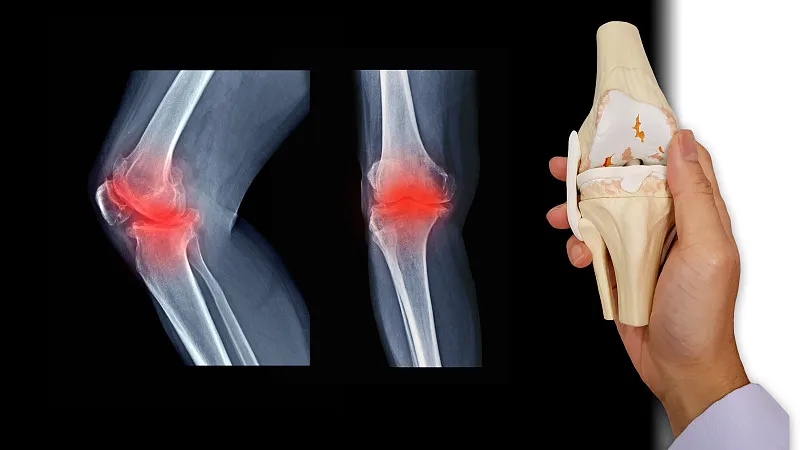

關(guān)節(jié)炎是一個通用術(shù)語,表示關(guān)節(jié)發(fā)炎。骨關(guān)節(jié)炎,俗稱磨損性關(guān)節(jié)炎,是最常見的關(guān)節(jié)炎類型。它與關(guān)節(jié)軟骨的破壞有關(guān),并且?guī)缀蹩梢园l(fā)生在身體的任何關(guān)節(jié)中。它通常發(fā)生在臀部、膝蓋和脊柱的負(fù)重關(guān)節(jié)中。它還會影響手指、拇指、頸部和大腳趾。

骨關(guān)節(jié)炎-也稱為OA-通常不會影響其他關(guān)節(jié),除非涉及先前的損傷、過度壓力或潛在的軟骨疾病。

軟骨是一種堅(jiān)硬的橡膠狀材料,覆蓋在正常關(guān)節(jié)的骨骼末端。它的主要功能是減少關(guān)節(jié)處的摩擦,起到“減震器”的作用。正常軟骨的減震特性來自其在受壓(壓平或壓在一起)時(shí)改變形狀的能力。

骨關(guān)節(jié)炎導(dǎo)致關(guān)節(jié)中的軟骨變硬并失去彈性,使其更容易受到損傷。隨著時(shí)間的推移,軟骨可能會在某些區(qū)域磨損,從而大大降低其作為減震器的能力。隨著軟骨退化,肌腱和韌帶伸展,引起疼痛。如果情況惡化,骨頭可能會相互摩擦。

如何診斷骨關(guān)節(jié)炎?

您的醫(yī)生可能會使用X光檢查來幫助確認(rèn)診斷并確保您沒有其他類型的關(guān)節(jié)炎。X 射線顯示發(fā)生了多少關(guān)節(jié)損傷。如果X射線結(jié)果不能明確指出關(guān)節(jié)炎或其他疾病,則可能需要進(jìn)行MRI以更好地觀察關(guān)節(jié)和周圍組織。